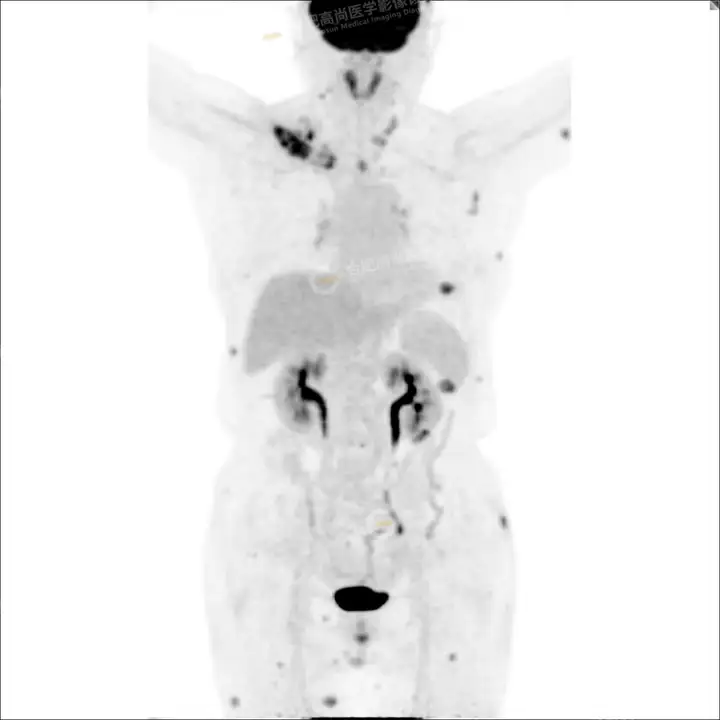

PETCT检查所示:图1、3-17全身多处(双上臂、胸背部、左侧乳腺、左侧腰部、腹壁、双侧臀部及双侧大腿)皮肤下结节及肿块样软组织密度灶,FDG代谢不同程度增高,双侧颈部、左侧锁骨区、纵隔内(1区)及双侧腋窝多发肿大淋巴结,FDG代谢明显增高,符合皮肤来源淋巴瘤。